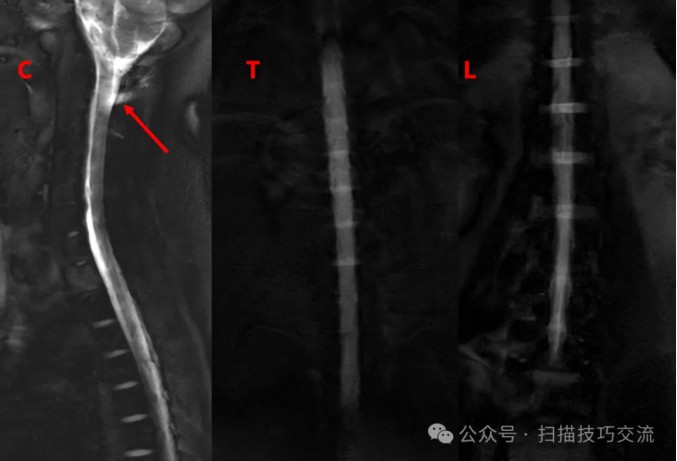

快速的脊髓水成像序列& #40;1s/slice& #41;,试一下,

颈2区域感觉不大对(长箭)。

加个COR 2D MRM对照一下。扫描参数界面:

来都来了,再加个3D MRM看一下,